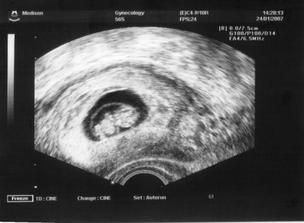

Jelikož se sen proměnil ve skutečnost, tak k nám přiletí čáp nebo vrána koncem velkých prázdnin 2007. Už jsem začali nakupovat, většinu věciček pro mimi kupuji v sekáči,jelikož se domnívám, že je úplná škoda utrácet penízky za nové oblečení,které je nekřesťansky drahé.Miminko stejně nic neunosí a ze všeho za chvíli vyroste.Takže si fakt vybírám a zatím se mi daří...Moc se těšíme...